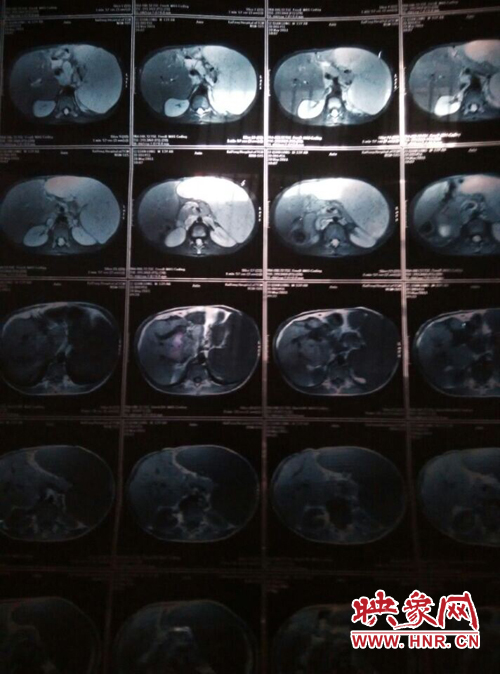

映象網(wǎng)商丘訊(記者 曾巖 代艷)他是一個(gè)花季少年,兩歲半時(shí)患上怪病,經(jīng)過(guò)漫長(zhǎng)的求醫(yī)之路查出是肝脾腫大,十幾年的看病之路,花了幾十萬(wàn),非但沒(méi)有醫(yī)好他的病,讓這個(gè)原本就貧困的家庭雪上加霜。

他叫李乾龍,今年16歲,家住寧陵縣城郊鄉(xiāng)李莊村,家里有四口人,目前在寧陵縣黨校就讀上高一,他一邊上學(xué)一邊看病,十幾年來(lái),他們跑遍了大小醫(yī)院,卻一直沒(méi)查出他的病因。16歲的他發(fā)育的還沒(méi)有13歲的弟弟高,肚子大的像個(gè)皮球,經(jīng)常身體發(fā)熱,全身無(wú)力,因?yàn)闆](méi)錢去大醫(yī)院檢查治療只得在家保守治療。